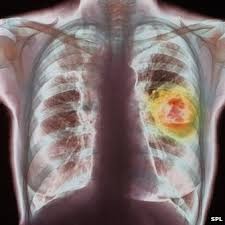

慶祝重生,共聚感恩|癌症康復者日特別聚會